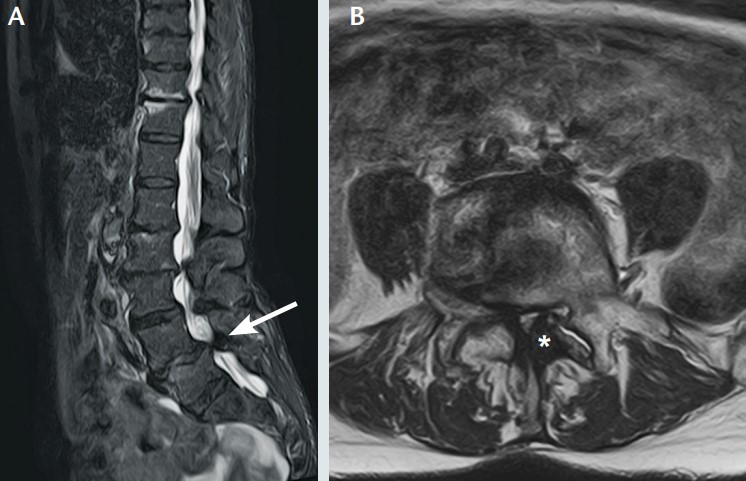

Imagerie par résonance magnétique chez une femme de 80 ans ayant un canal lombaire rétréci en L4L5.T2, coupe sagittale (A) et coupe coronale (B).